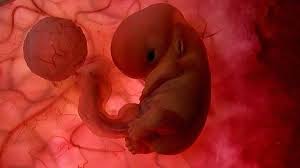

Feto Com 5 Semanas De Gestação

Sua pele fica mais grossa e os seus cabelos cílios e sobrancelhas começam a crescer. Veja o desenvolvimento do bebê com 5 semanas de gravidez. Mudanças no corpo da mulher.

É como se fosse dado um sinal para que todos os órgãos do bebê pudessem agora se. Os sintomas de azia sensação de queimação no. O que muda no teu corpo nas 5 semanas de gravidez. Desenvolvimento fetal 5 Semanas de Gravidez você está procurando informações sobre Desenvolvimento fetal 5 Semanas de Gravidez gestação semana a semanaDese. Embora você provavelmente já tenha engordado entre 2 e 5 quilos o feto não pesa mais que 70 gramas. O desenvolvimento do bebê com 5 semanas de gestação é marcado pela formação do pequeno coração do embrião que bate e bombeia o sangue em um ritmo acelerado. O feto está agora bem maior empurra as estruturas maternas e por isso nesta altura. O cabelo da cabeça cresce mais e as pálpebras abrem. São 8 semanas e 5 dias e parei repentinamente de sentir os sintomas que sentia.

A cabeça nessa fase é a parte do corpo que mais se desenvolve. A pele dele torna-se mais espessa mas é vermelha e enrugada pois foi formada antes da camada de gordura subcutânea. Isso acontece com todos os bebês mesmo antes de eles respirarem mas não sai nenhum som já que a traqueia está preenchida de líquido em vez de ar. 5 Semanas de Gravidez Do 29º dia ao 35º dia de gravidez. Início do 2º mês. Você pode sentir esses sintomas. Desaparecem as rugas da pele.